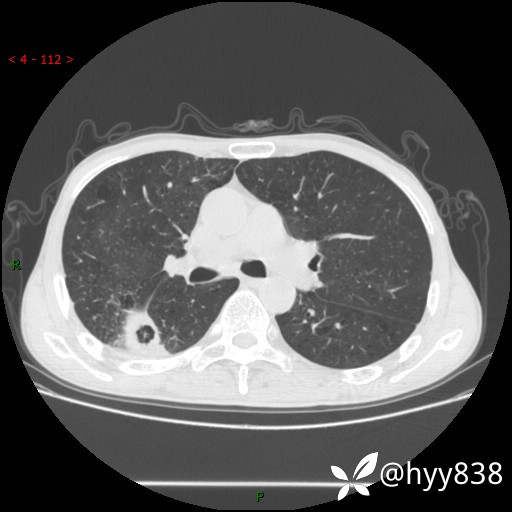

老年男性,肺团片状占位+体重下降,肿瘤 VS 真菌 VS 细菌,看看你的意见--结果公布~

简要病史:患者7天前无明显诱因出现咳嗽咳痰,咳绿色、褐色痰,吸烟后加重,伴心慌、胸闷,无畏寒发热,无头晕头痛,无鼻塞流涕,无痰中带血及咯血,无胸痛、呼吸困难,无全身酸痛,为求进一步诊治于我院就诊,门诊完善胸部CT提示“右下肺团片状影,考虑肿瘤?感染?”,门诊以“咳嗽待查”收住入院。 起病以来,患者精神、饮食、睡眠尚可,大、小便正常,体力下降,体重下降8斤。空腹血糖:6.42mmol/L。

辅助检查:CT

临床诊断:肿瘤?感染?

胸部CT平扫